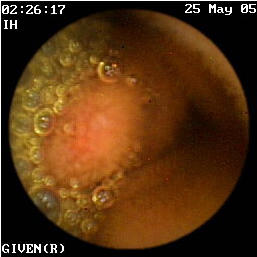

Η κάψουλα έχει επίσης ιδιαίτερη αξία στην ανεύρεση της εστίας της αιμορραγίας αγνώστου αιτιολογίας στη νόσο του Crohn (εικόνες 1,2). Οι Legnaniκαι συν του16 εκτίμησαν 11 ασθενείς με νόσο Crohnκαι αδιευκρίνιστη αιμορραγία και προσδιόρισαν την ακριβή αιτία της στους 9 από αυτούς.

1  2

Eικόνα 1. Βαριά φλεγμονή του βλεννογόνου             Εικόνα 2. Αυτόματη αιμορραγία ειλεού σε ασθενή

με σχηματισμό ψευδοπολύποδα.                             με γνωστή νόσο Crohn